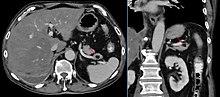

| An MRI of a patient with benign familial macrocephaly (male with head circumference > 60cm) | |